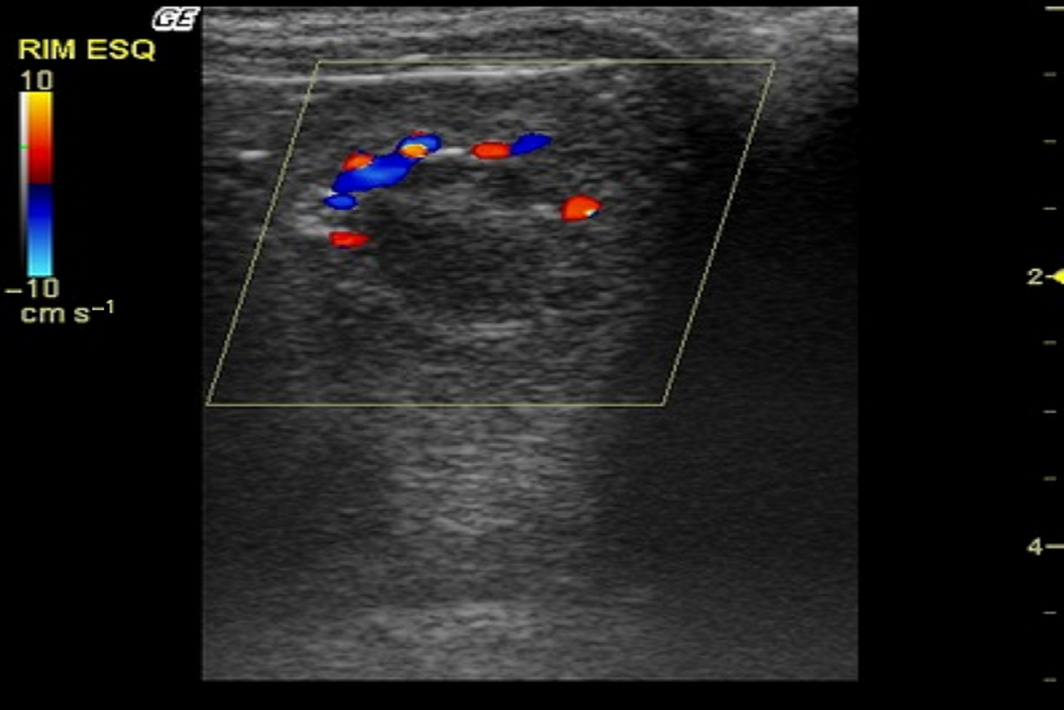

After the B-mode examination, the kidneys were assessed by colour Doppler mode. The hilar and intrarenal vasculature was visualized. At the hilum, it was possible to define the renal artery and renal vein. Cortical and medullary regions were observed presenting several vascular branches, both arterial and venous, throughout the renal parenchyma (Fig. 3). No sign of turbulence was observed. Spectral Doppler mode examination measured systolic peak velocity (Vs), end diastolic velocity (Vd) and resistive index (RI [range: 46–56, mean 53]) of the renal artery. The spectral Doppler measurements of the left renal artery are described in Table 1.

|

Figure 3. Color Doppler sonogram of the left kidney in an Alouatta fusca. Cortical and medullary regions were observed demonstrating arcuate vessels at the cortico-medullary junction. |